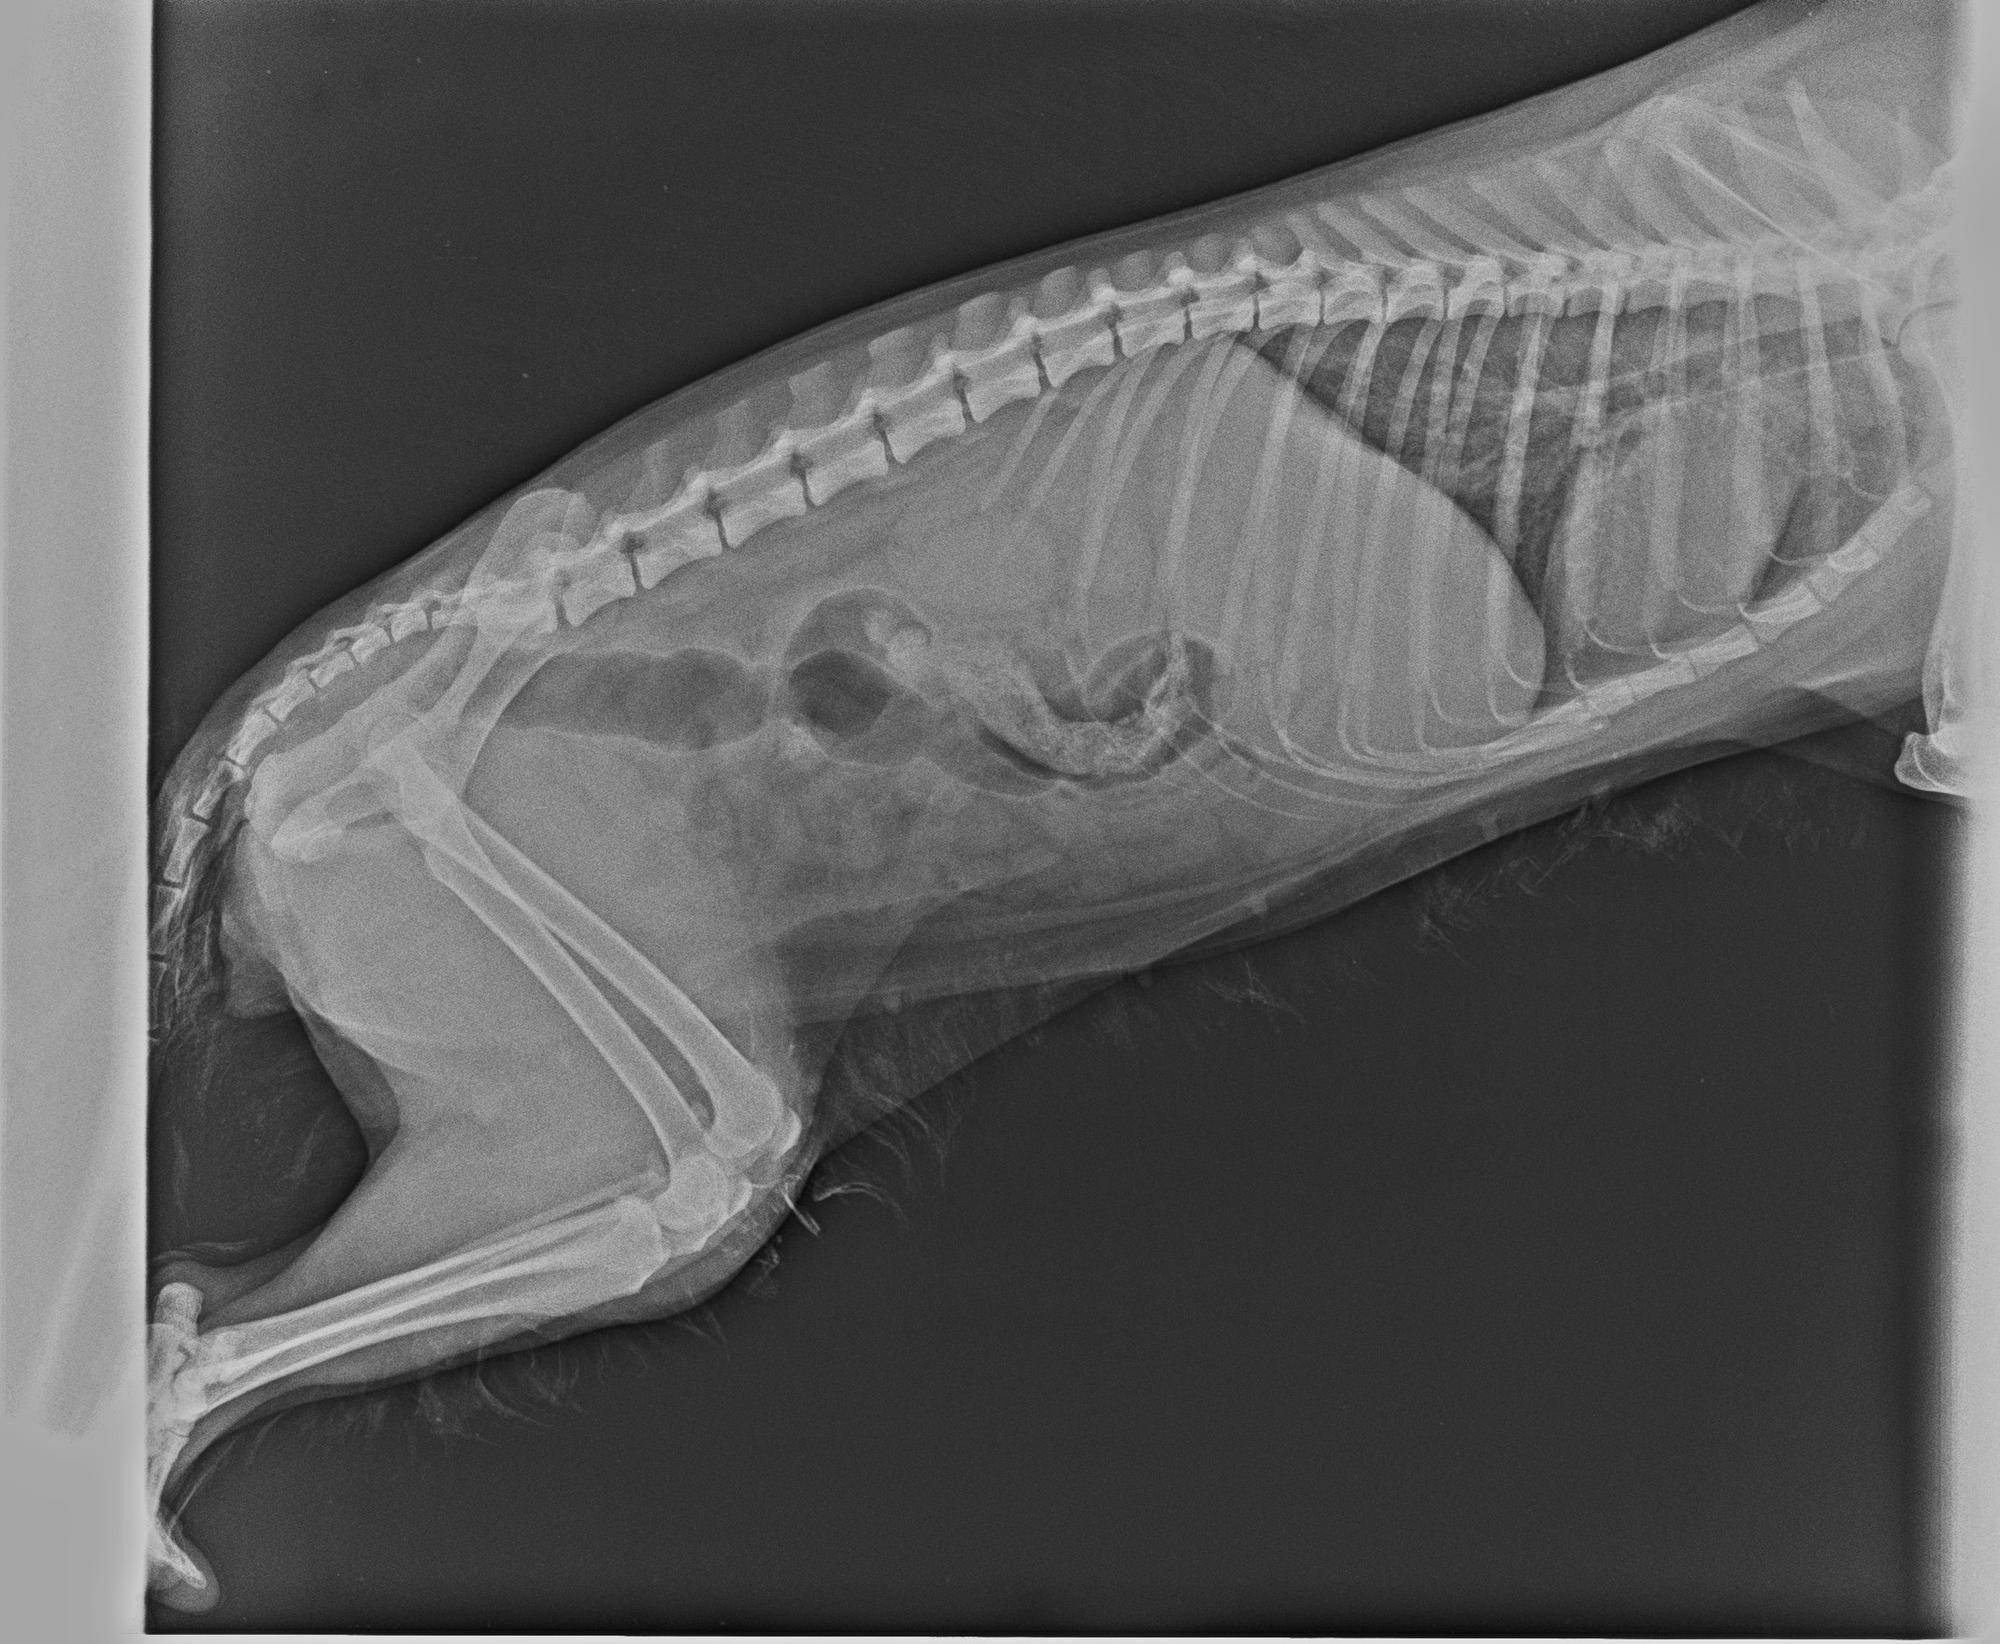

その際撮ったレントゲン写真がこちらです。

骨折は見当たらなかったものの、左後肢の膝関節がものすごく腫れていました。

あまりに腫れているので、そのときは動かすこともできませんでした。

そして腫れて動かなかった左後肢の膝関節がグラグラしているのを認め、脱臼していることがわかりました。